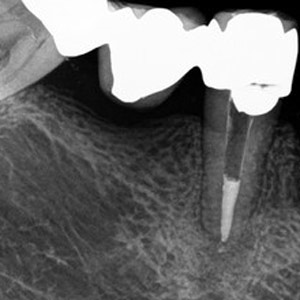

NON-SURGICAL

Oftentimes, our patients need non-surgical treatments that require minimal intervention. This intertwines with our belief that preventative maintenance and regular dental care can minimize the need for surgeries. You can rest assured that our highly trained and experienced team consistently provides the highest quality endodontic treatments and assistance available in the North Shore.